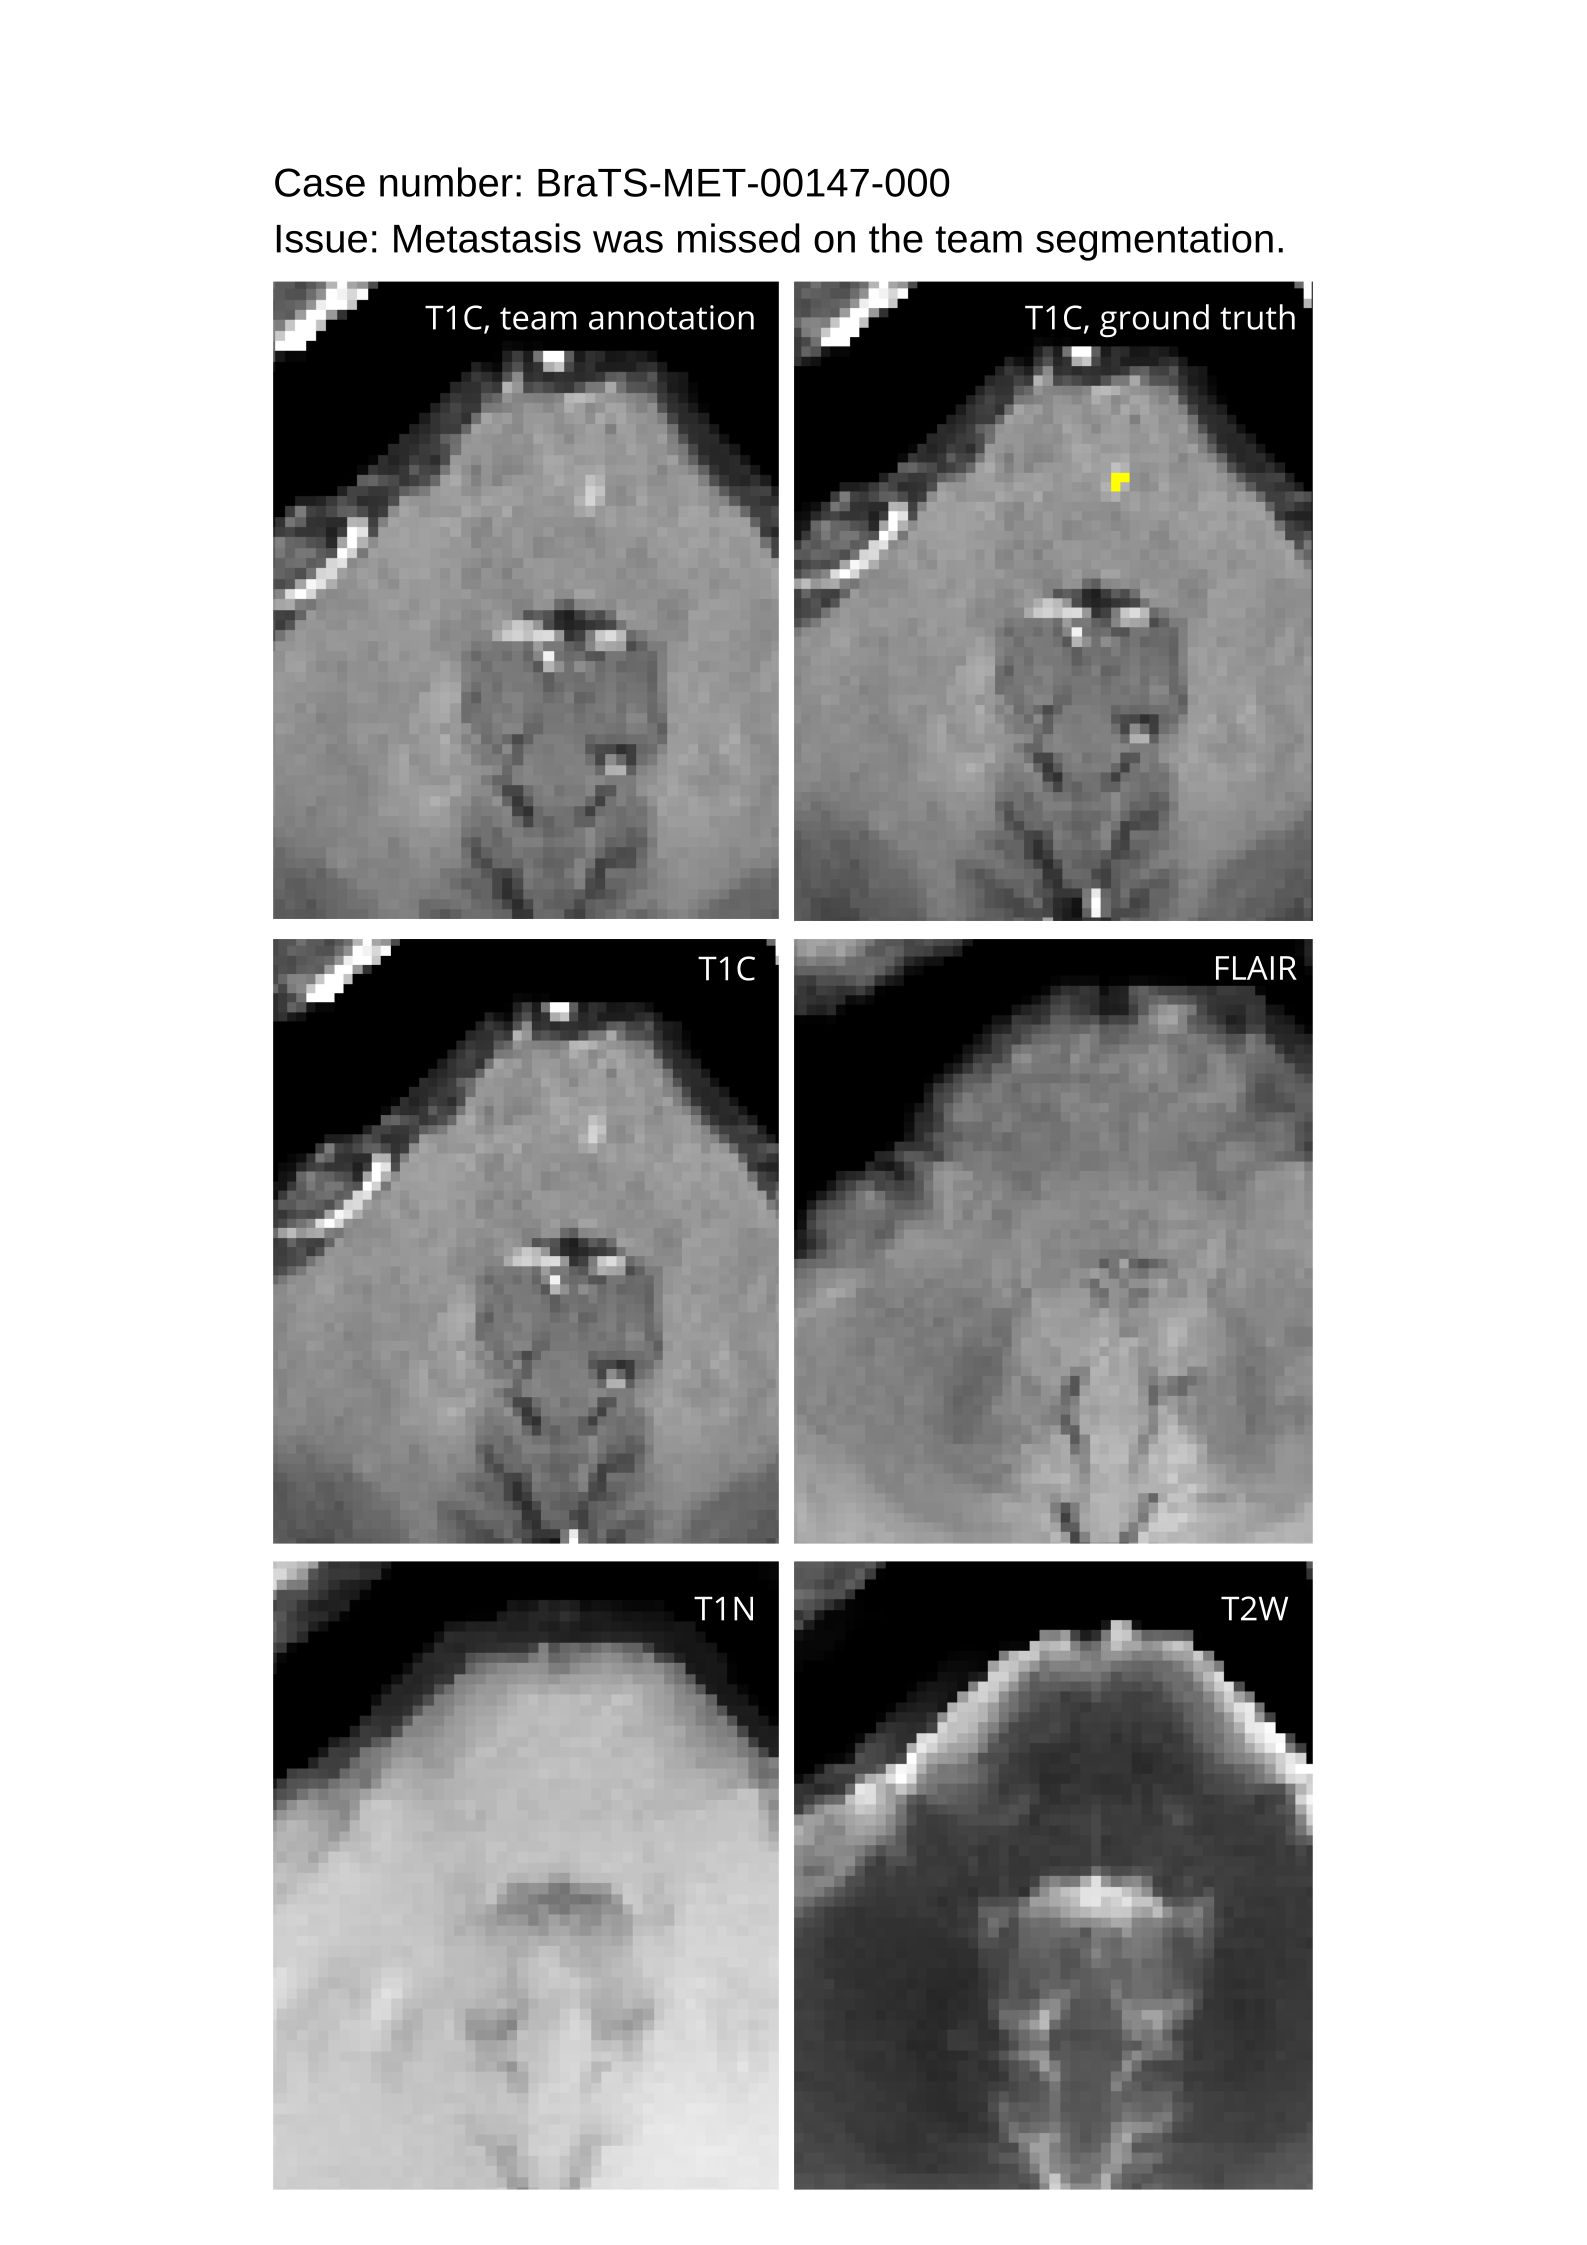

4.9 Common Errors of Automated Segmentations

Based on observations from previous BraTS challenges, common errors in automated segmentations were identified. The most typical errors in the current challenge included:

1. 1.

Automated algorithms missing small metastases. Enhancing metastasis was fused using the minority voting algorithm to aggregate all enhancing tumor voxels identified by the three algorithms. However, many small metastases were missed and were manually segmented by neuroradiology attendings.

2. 2.

Segmentation of white matter changes from microvascular disease. Peritumoral edema segmentations were checked by neuroradiology attendings and modified.

3. 3.

The segmentation of non-enhancing lesions that have intrinsic T1 hyperintensity. Voxels with intrinsic T1 hyperintensity were manually removed from ET segmentations.

These insights led to specific adjustments in the annotation process to enhance accuracy.